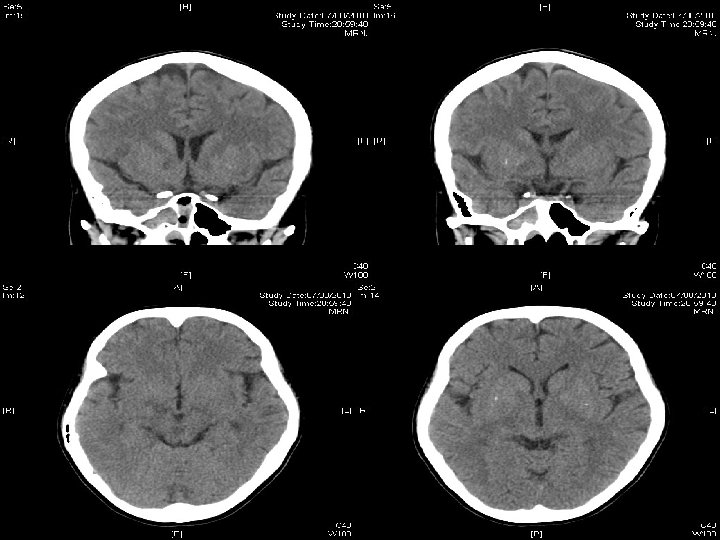

Admit M&G of hospital A No ocular movement deficit n Normal facial sensation/ hearing n Tongue movement intact n Poor gag reflex + bilateral LMN VII palsy n Tandem-walking unsteady n WC 13. 4 (80% neutrophil); normal R/LFT n ESR 73; CRP 27 n CT Brain: ? Right pons hypodense spots n

Treat as ? Bickerstaff encephalitis IV ampicillin + IV Acyclovir > 9/7 to 15/7 n IVIG at 0. 4 g/ kg weight > 14/7 to 18/7 n Hydrocortisone 100 mg Q 8 H > 20/7 to 25/7 n Prednisolone (tapering dose)> 26/7 to 5/8 n CT brain 7 th Aug putamen lesions+ n Rt dilated pupil FU eye as uveitis n She wants to withhold invasive treatment/ workup if cancer diagnosed n

Contrast CT brain on 27 th Aug

Searching for an answer, again…. . n n n n n 9 th July: Plain CT Brain (Hospital A) 7 th Aug: Plain CT Brain (Hospital A) 25 th August: Plain CT Orbit (Hospital A) 27 th August: Contrast CT brain + Sinus 4 th September: MRI brain + brainstem 4 th September: Plain CT brain 10 th September: Contrast CT brain 11 th September: Plain CT sinus 15 th September: MRI brain + DWI

Summary of progression • June/ 2010 n • July/ 2010 n • Early Aug/ 2010 n • Late Aug/ 2010 n • Sept/ 2010 n Lt face weak Bulbar palsy Dilated Rt pupil and uveitis Endophthalmitis and high fever Deep coma, tetraplegia, high fever n n n Nil imaging Facial neuritis Bilateral basal ganglia change Bilateral temporal + BG + thalami + pons